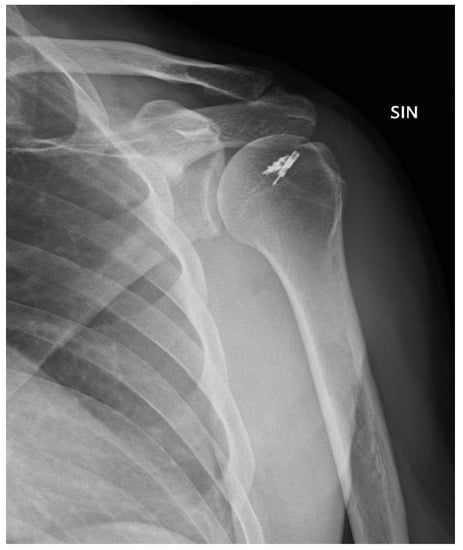

Posterior Shoulder Dislocation with Engaging Reverse Hill–Sachs Lesion: A Retrospective Study of Ten Patients Treated with Arthroscopy or Open Reduction and Stabilization

2. Materials and Methods

3. Results